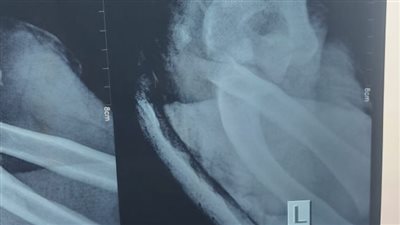

قال الدكتور هشام مجدي سليمان، استشاري جراحة العمود الفقري بكلية الطب جامعة القاهرة، إن أسباب اعوجاج العمود الفقري تختلف من مرحلة عمرية لأخرى، موضحًا أن 80% من حالات الأطفال تكون أسبابها غير معروفة، لكنها قد تكون ناتجة عن عيوب خلقية أو أمراض عصبية.

وفيما يتعلق بالعلاج، أوضح “سليمان”، خلال لقائه مع الإعلامية مروة مطر، ببرنامج “أنا والناس”، المذاع على قناة “النهار”، أن التدخل الجراحي يتم فقط في الحالات التي تتجاوز فيها زاوية الاعوجاج 40 درجة، مشددًا على أهمية تأجيل العملية لما بعد سن البلوغ لتجنب التأثير على نمو الطفل، وفي الحالات البسيطة، يُمكن استخدام الحزام الطبي لإبطاء تطور الاعوجاج وليس لعلاجه بشكل جذري.

وأكد أن الجراحة يُمكن أن تتم عبر فتح جراحي كبير أو باستخدام تقنية المنظار التي تسمح بإصلاح الاعوجاج بفتحات صغيرة جدًا، مشيرًا إلى أن نسبة الأمان في كلتا الطريقتين تتجاوز 99%، مع وجود أجهزة لمراقبة الأعصاب أثناء العملية، وبعد العملية، يُمكن للمريض العودة لحياته الطبيعية في غضون أسابيع قليلة.